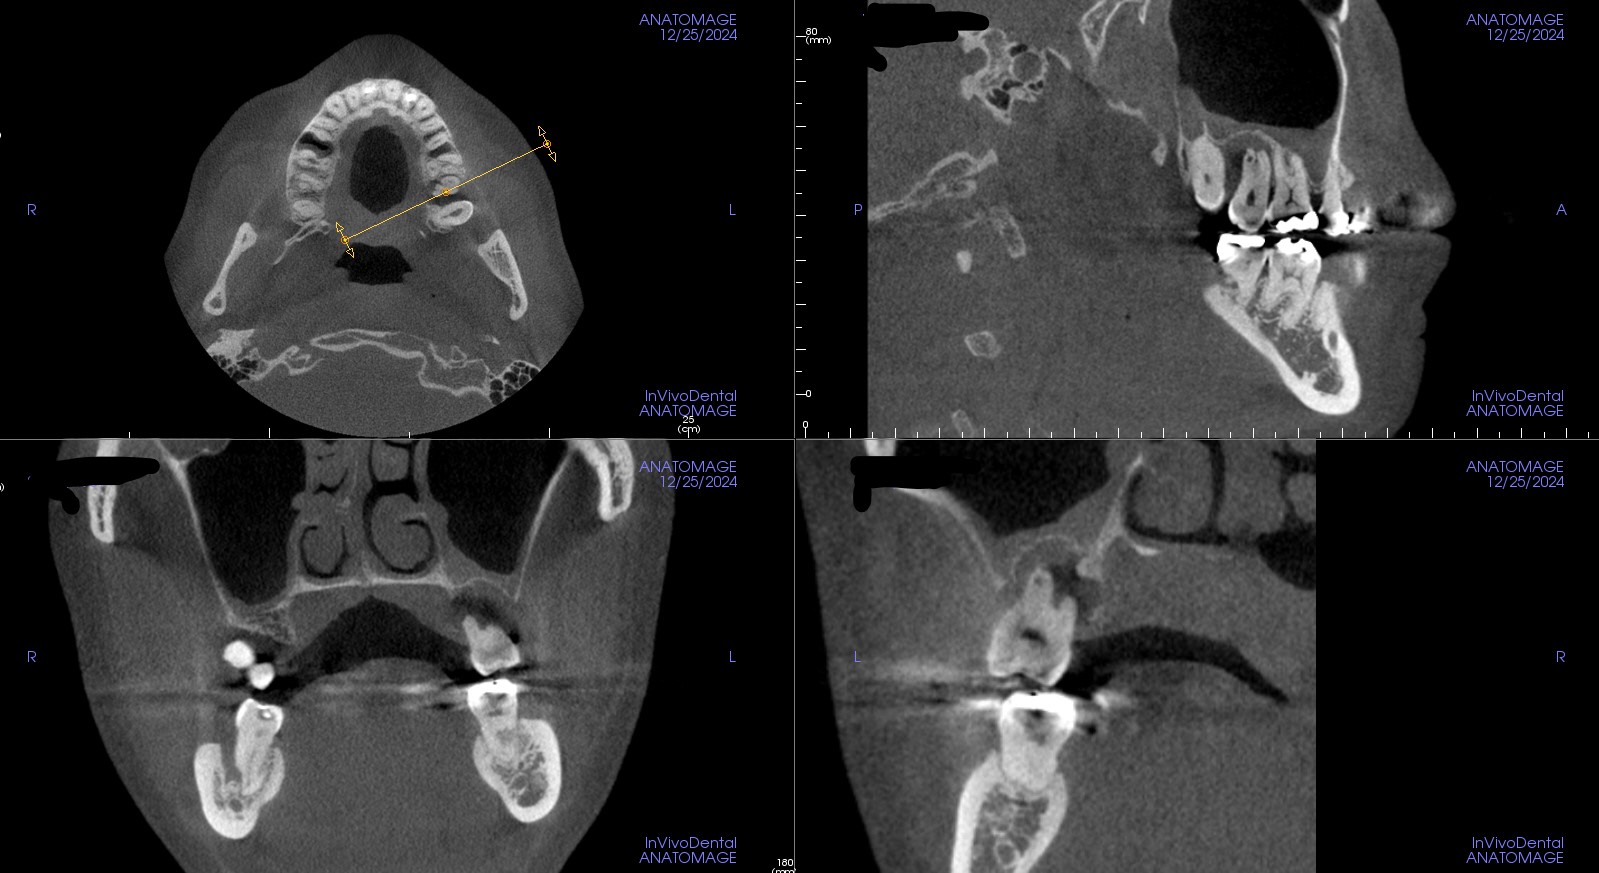

術前

左上の奥歯がグラグラの状態でした。

全体の歯石取り(歯周初期治療)を行いましたが、回復が見られなかったので、

再植手術をすることとしました。